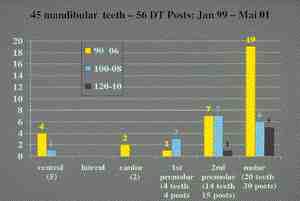

Background – Major Depressive Disorder (MDD/depression) is a mental illness characterized by marked sadness, and/or a loss of interest or pleasure in daily activities may be accompanied by weight loss, sleep disturbance, difficulty concentrating, and a high suicide rate. The disorder is very common in Canada with a lifetime prevalence rate of approximately 24%. Unfortunately, half of all patients with depression never see a physician and therefore go undiagnosed and untreated. Clinical Implications – Individuals under treatment for depression and those whose illness has not been diagnosed often present to the dentist with significant oral disease. Dentists need to be cognizant of how to safely and compassionately provide care to those already receiving mental health services. They must also be familiar with the psychiatric symptoms of the disorder so that they can effectuate a timely referral to a physician of those with occult or relapsing disease. Depression is frequently associated with a disinterest in performing oral hygiene, a cariogenic diet, rampant dental decay, advanced periodontal disease, and oral dysesthesias. Antidepressants used to treat the disease cause the xerostomia and may increase the severity of dental disease. Appropriate dental management necessitates a vigorous preventive dental education program, the use of artificial salivary products, antiseptic mouthwash, daily fluoride mouth rinse, and special precautions when administering local anesthetics with vasoconstrictors and prescribing analgesics. Conclusions — Dentists invoking appropriate precautions can usually provide a full range of services to individuals with major depressive disorder thereby enhancing patient self esteem and contributing to the therapeutic milieu.